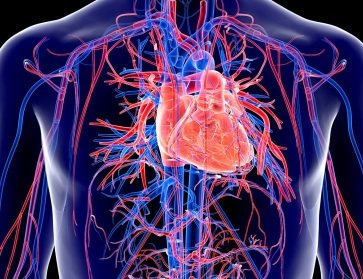

Cardiac Surgery

Cardiovascular